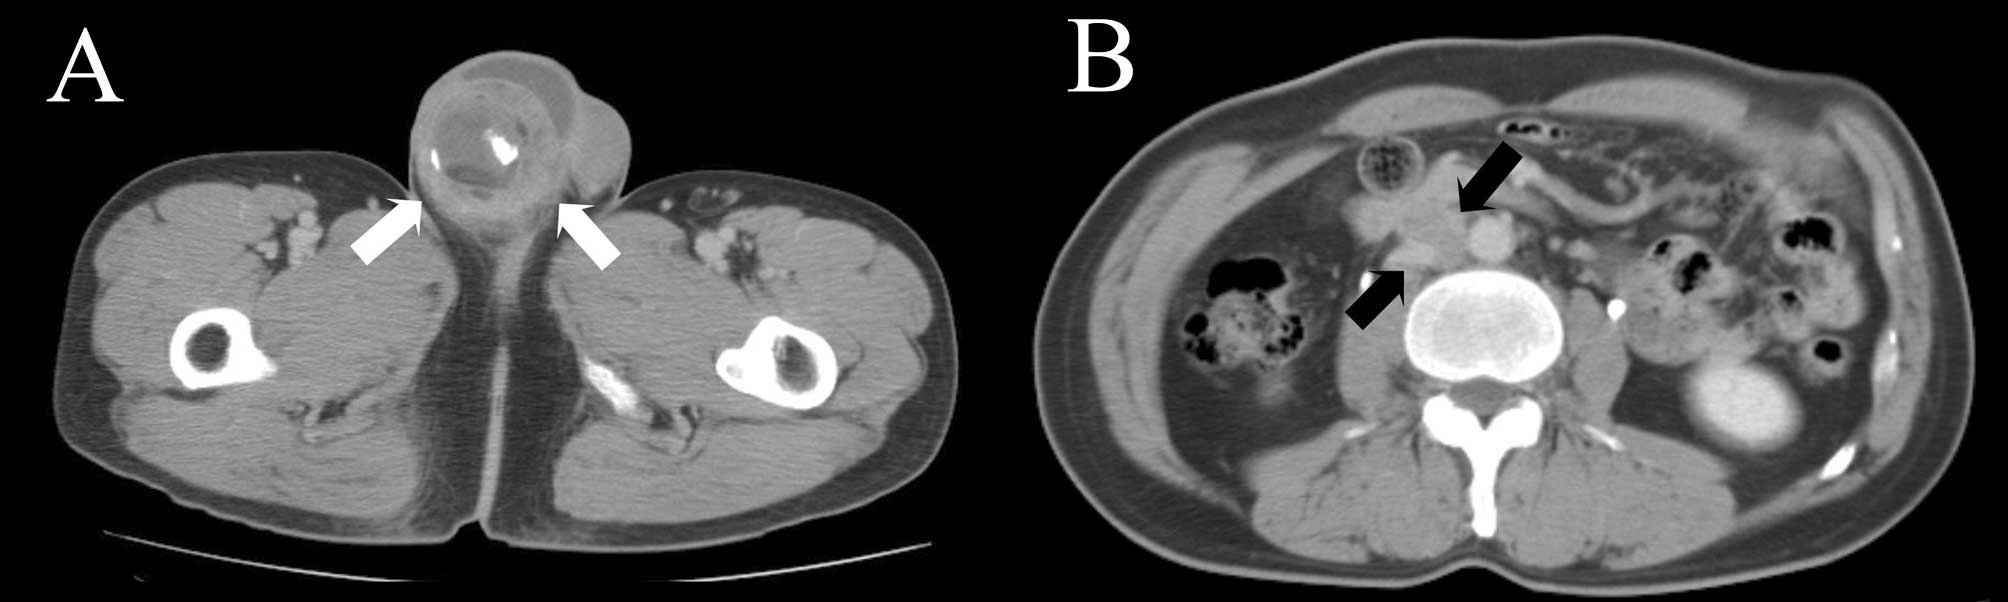

We received the ethics committee’s approval and the patient’s written informed consent. Ultrasonography showed a right hydrocele with the heterogeneous mass. Computed tomography (CT) revealed a right testicular mass measuring 5 cm and multiple aortocaval and paraaortic lymphadenopathies (Fig. 1). A bone scan showed increased radioisotope uptake at the 2nd and 4th lumbar vertebrae, sternum, right scapula and ribs (Fig. 2).